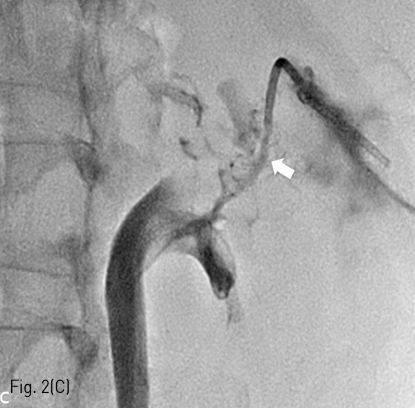

Fig 2C

(C) Fistulography obtained after successful catheterization for urinary fistula shows direct connection (arrow) between the renal calyx and urinoma cavity.

우측 신장 부분 절제술 주변 large urinoma에 대해서 경피적 배액술을 먼저 시행하기로 계획하였고, 이에 Rt. lateral abdominal wall을 국소 마취한 후 right partial nephrectomy site 주변부 urinoma를 21G needle (Tae Chang Industrial, Taegu, Korea)로 천 자 하고, 8.5Fr pigtail catheter (Cook, Bloomington, IN)를 삽입하여 urinoma 배액술을 시행하였다 (Fig. 2A). 배액술 이후 경과 관찰하였을 때, 배액관을 통해서 160cc/day의 요누출이 지속되어 배액술 시행 12일째 urinary leakage에 대해서 embolization을 시행하기로 하였다. 배액술을 통해 cavity size 가 감소한 urinoma를 초음파 유도 하에 21G needle로 천자하고, 5Fr Kumpe catheter와 2.0Fr microcatheter (Progreat, Terumo, Tokyo, Japan)을 이용하여 partial nephrectomy site로부터 urinoma로의 fistulous tract을 찾는데 성공하였고 (Fig. 2B), 조영제를 주입하였을 때 뚜렷한 fistulous tract이 존재함을 확인하였다 (Fig. 2C). 이후 해당 fistulous tract을 MicroNester coil (3mmx2cmx6ea, Cook)을 이용하여 embolization 시행하였고, urinoma cavity를 N-Butyl cyanoacrylate (Histoacryl, B. Braun, Rubi, Spain) 2 vial 과 iodized oil (Lipiodol Ultra Fluide; Guerbet, Roissy, France) 1:1 mixture를 사용하여 obliteration 하고 pigtail catheter는 제거하였다 (Fig. 2D). 시술 직후 시행한 초음파에서 residual urinoma cavity는 관찰되지 않았다.